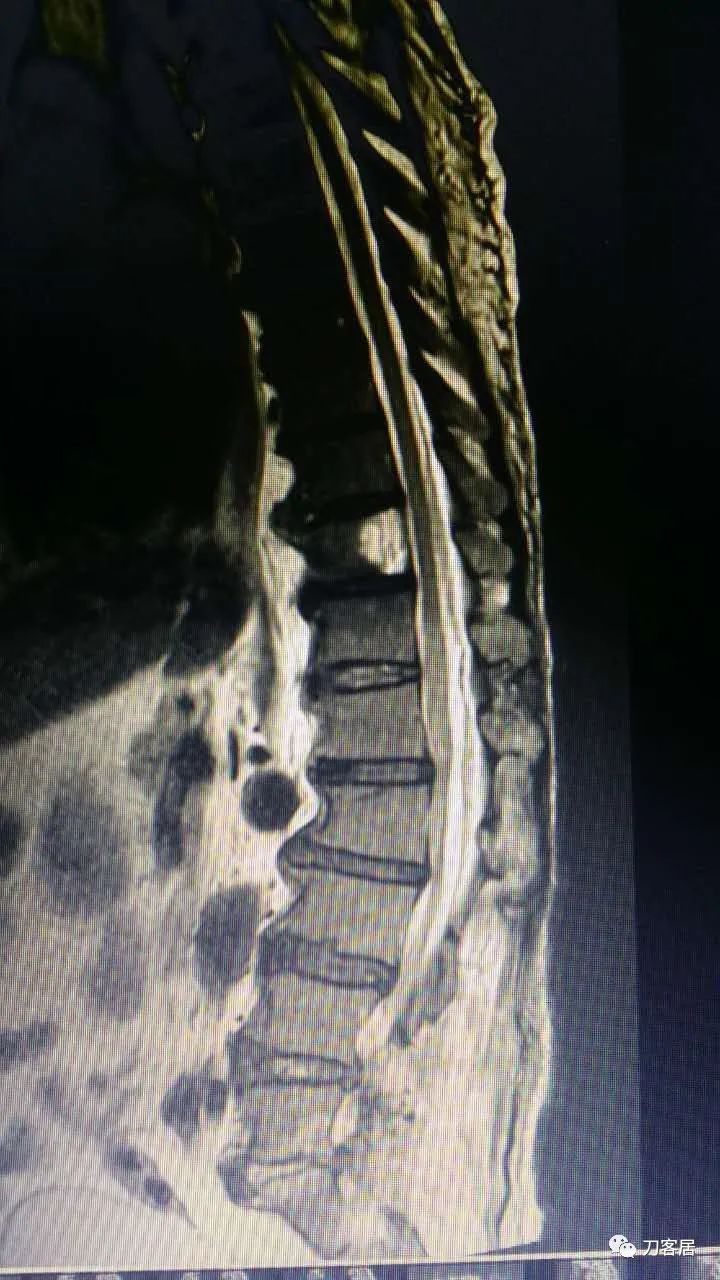

加注图14. 胸9-10椎管内后方高信号占位病变,考虑血肿形成。

加注图15. 胸9-10椎管内后方高信号占位病变,考虑血肿形成。

加注图16. 胸9-10椎管内后方高信号占位病变,考虑血肿形成。

加注图17. 胸9-10椎管内后方高信号占位病变,考虑血肿形成。